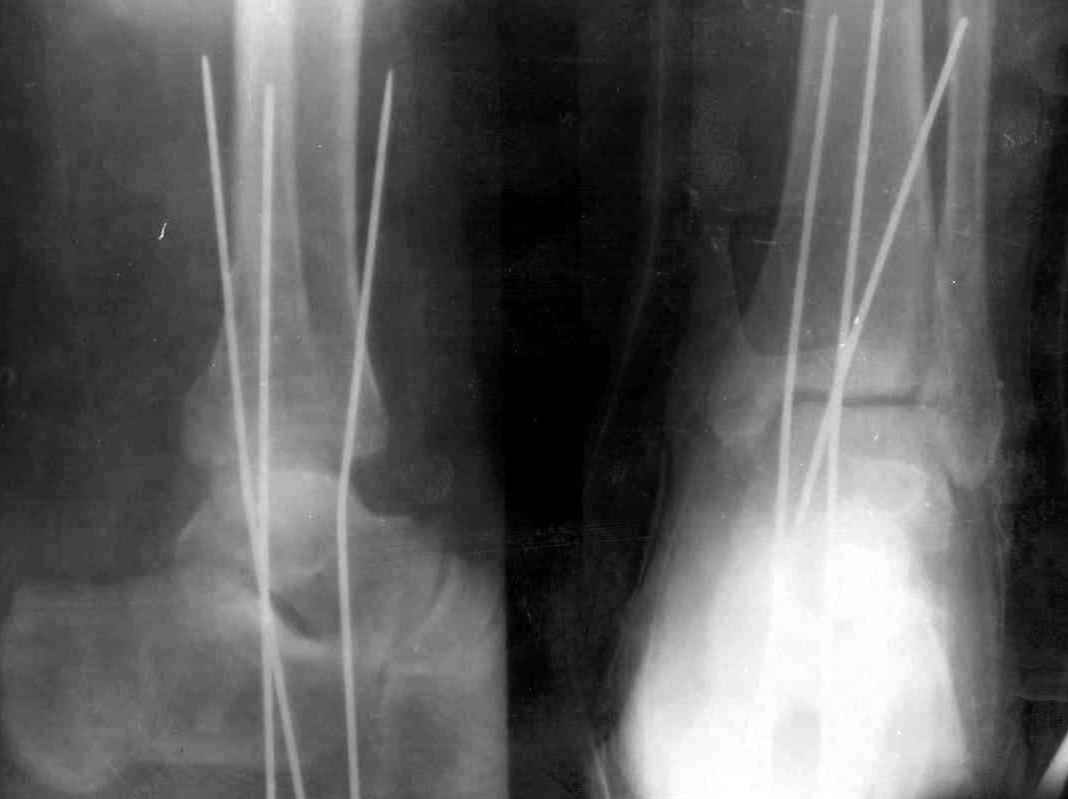

На 4-й неделе убрал спицы, с 7-й недели начал ЛФК, дозированную нагрузку, физиопроцедуры, массаж. Назначил хондропротекторы. Получилось вот что.

Rg-05.JPG

Удалены спицы, а гипса не было? 3-х лодыжечный перелом фиксировать 4 недели недостаточно. Что и подтверждается на последнем снимке - есть тенденция к подвывиху кнаружи, кзади... Что будет дальше, когда пациент начнет давать полную нагрузку?

Малоберцовая выглядит коротковатой. Профиль как-то мутный. Вообще, неплохо было бы сделать снимки в сравнении со здоровой.